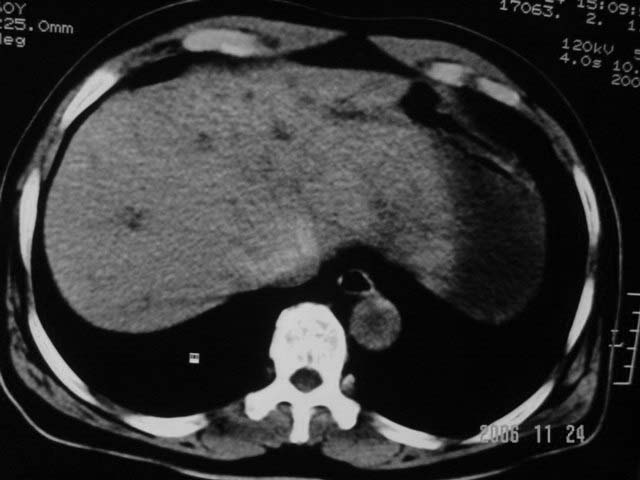

标题: CT5395:男、60岁,皮肤、巩膜黄染伴上腹部疼痛20天 [打印本页]

标题: CT5395:男、60岁,皮肤、巩膜黄染伴上腹部疼痛20天

劳烦各位老师看一下最后一幅箭头指的地方是不是胆总管结石.ct值约63hu.

感觉不是结石可能,与上一层面联系应该是门脉区影像,图像显示不佳,胆总管显示不清[特别是胰头以上段],目前影像只能说肝内外胆管扩张,胰管扩张,胆囊扩大。提示胆总管远端梗阻。可考虑肿瘤或结石所致

胆总管内结节状高密度灶,边缘隐约可见低密度环绕,首先考虑结石伴肝内胆管扩张; 2、胆囊增大,胆囊炎

肝内外胆管及胰管均示有扩张,胆囊增大.提示胆总管远端梗阻,可考虑肿瘤或结石或肿瘤伴结石,建议强化扫描